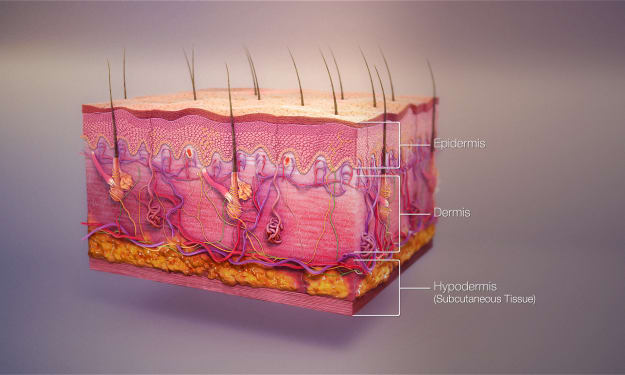

Do our skin have these ???

Title: The Integumentary System: Unveiling the Marvels of Skin, Hair, and Nails Introduction Step into any store, and you'll encounter a vast array of soaps, lotions, conditioners, and polishes dedicated to grooming our skin, hair, and nails. While some view these products as mere vanities, they are, in fact, the tools that care for, maintain, and decorate our integumentary system. Beyond their cosmetic applications, these resilient tissues serve a multitude of functions, many of which go unnoticed. However, when we do notice the workings of our integumentary system, it is often due to uncomfortable or unsightly conditions. This article aims to shed light on the vital functions of our integumentary system, emphasizing the importance of its care and maintenance for overall health.

By RAMYA VENUGOPAL3 years ago in Humans

What about SKIN ?

Title: The Remarkable Complexity of Your Skin: A Closer Look at the Body's Largest Organ Introduction When we think of organs, we often imagine the heart, liver, or lungs. However, we tend to overlook the largest organ of all—our skin. Beyond its external appearance, the skin serves crucial functions, such as protection, temperature regulation, fluid balance, and even vitamin D synthesis. Composed of three layers—the epidermis, dermis, and hypodermis—each with its own unique set of cells, the skin is a remarkable organ that deserves recognition and understanding.

By RAMYA VENUGOPAL3 years ago in Humans